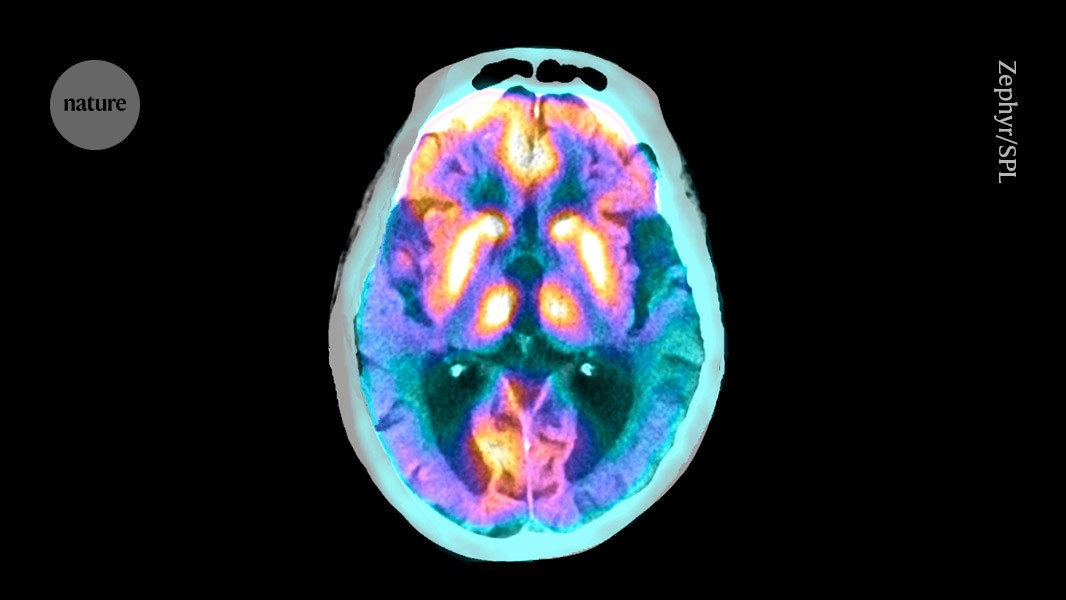

Credit: Zephyr/Science Photo Library

A group of specialized cells play a crucial part in clearing toxic proteins from inside the brain1. But in people with Alzheimer’s disease, these cells malfunction, leading to the build up of tau proteins — a hallmark of the disease.

Tanycytes, specialized cells that line the third ventricle of the brain, are unique because they are in direct contact with both the bloodstream and the cerebrospinal fluid (CSF). This means that they can circumvent the blood–brain barrier to allow molecules into and out of the brain. “Tanycytes are highways for the brain,” says Vincent Prévot, a neuroendocrinologist based in Paris at Inserm, the French National Institute of Health and Medical Research.